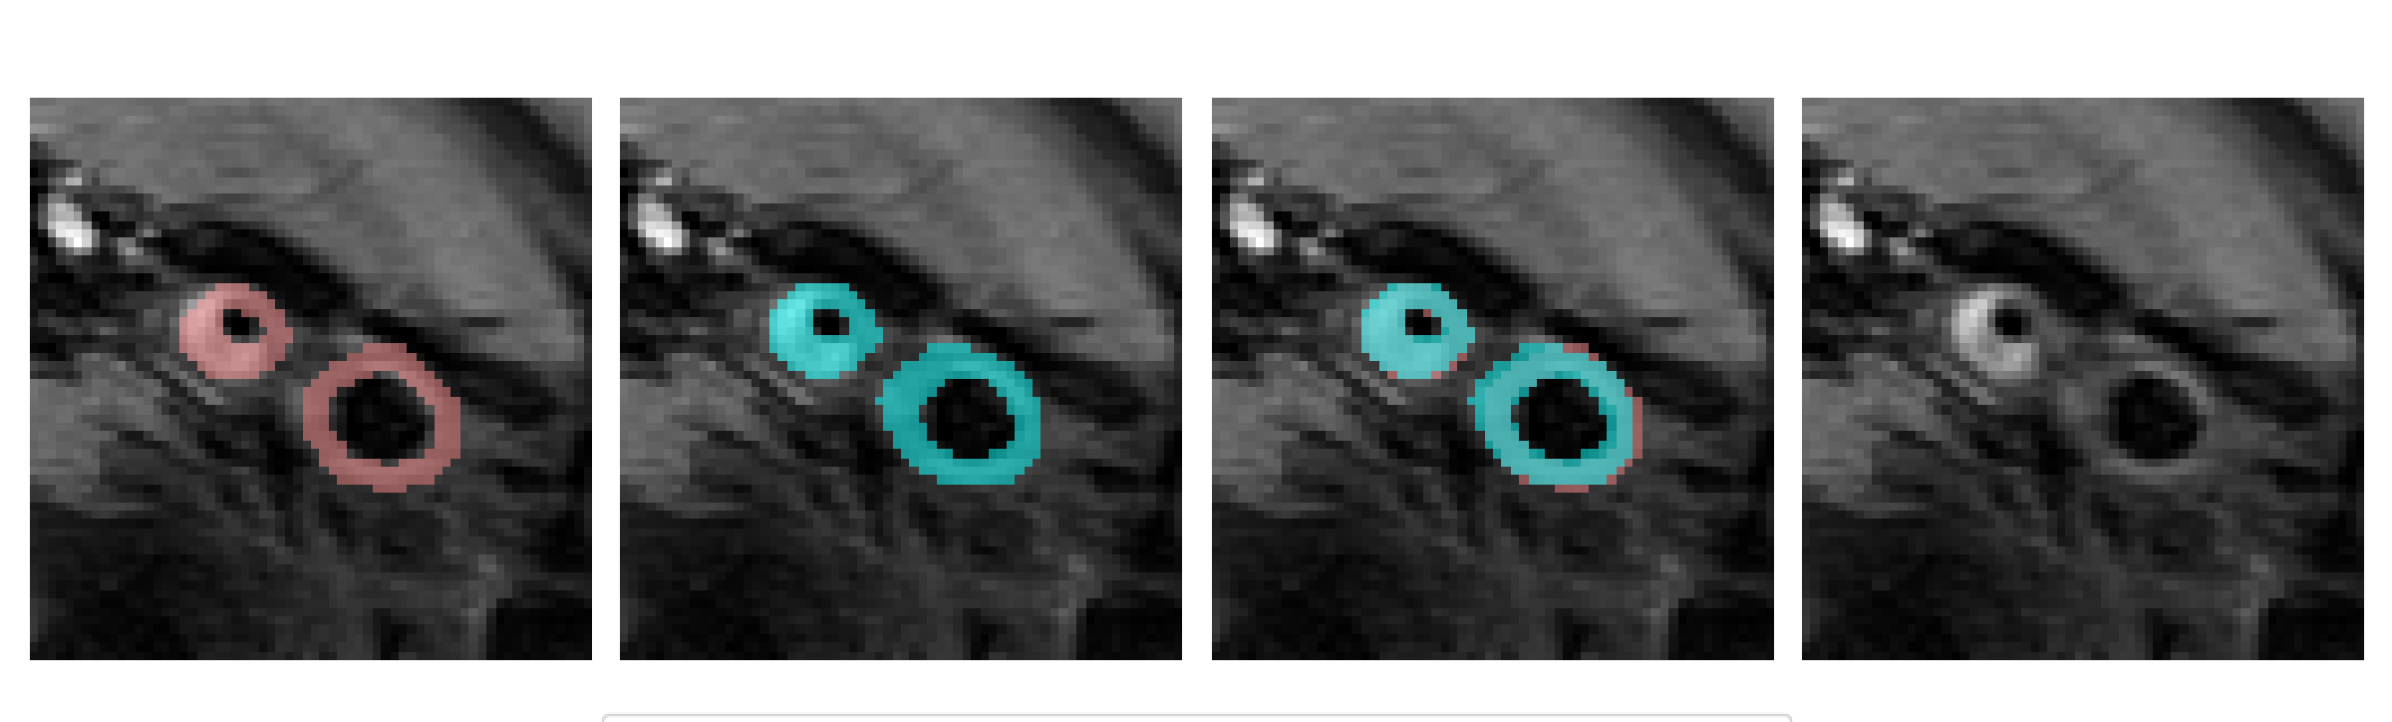

In Figure 7 we present exemplary outputs of our U-Net model in combination with bottleneck fusion for the binary case in comparison with the ground truth mask. The model was trained using image slices from 16 patients, while slices from 4 additional patients were used for validation and another 4 for testing. The predicted segmentation masks demonstrate a strong correspondence with the ground truth annotations provided by radiologists. In particular, the predicted masks accurately capture the target regions with minimal deviations, effectively delineating the carotid artery vessel wall and plaque. Not only do they successfully identify the intended structures, but they also align more closely with the underlying images. For instance, in the last example of Figure 7, the model correctly separates the two arteries, highlighting its accuracy.

where denotes the prior loss function that is applied to the predictions calculated for the supervised loss and a weighting coefficient. The prior function that is used within the prior loss function is also applied to the network output predictions and defined to ensure that the number of connected components (carotid artery vessels) found on each side of the image is restricted to a minimal number of one and a maximal number of two, reducing the false positive identification of other tissue structures. Additionally, the prior function enforces approximate symmetry by ensuring that the centers of the detected carotid arteries are approximately on the same horizontal line. In Figure 5, the left and right carotid artery vessel walls (and plaques) are displayed. The reason for enforcing only approximate symmetry of the two carotid arteries is that we observed that pathological changes, such as carotid artery plaques, and thus also the shape of carotid artery vessel walls can be highly non-symmetric, Figure 5(a). Further, also the bifurcation of the carotid artery may not always be symmetrical, Figure 5(b). For this, we constructed a geometric prior that accounts for natural asymmetries by focusing on positional alignment rather than shape constraints.